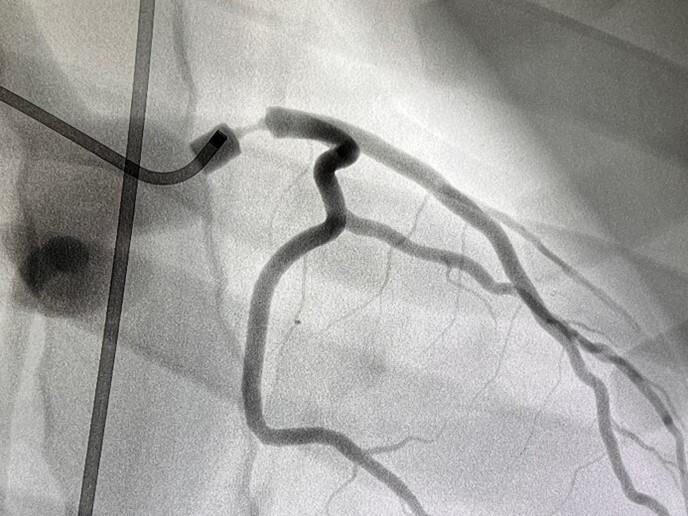

Abb. 3 Bifurkationsstenose

Abb. 3: Bifurkationsstenose (Mentice Vist)